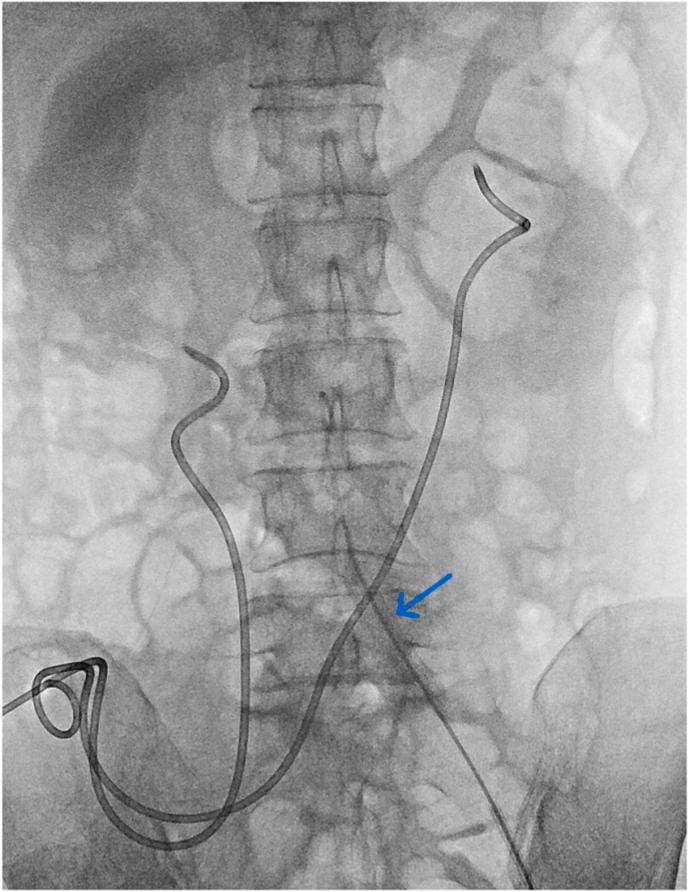

A 56-year-old female experienced massive pulsatile bleeding from the left ureter during routine ureteral stent exchange. She had a history of radical cystectomy and bilateral stent insertion due to uretero-intestinal strictures. Upon stent removal, sudden bleeding through the urostomy led to hypovolemic shock. Urostomy site compression stabilized the patient, and CT revealed suspected ureteroarterial fistula. Angiography confirmed the diagnosis. Covered stent placement in the external iliac artery resolved the condition. No recurrence was observed during a three-year follow-up. Prompt tamponade followed by endovascular intervention can be life-saving in such cases.

一名56岁女性在进行常规输尿管支架置换时,左侧输尿管出现大量搏动性出血。她有根治性膀胱切除术和因输尿管肠道狭窄而双侧置入支架的病史。取出支架后,经造口突然出血导致低血容量性休克。造口部位压迫使患者病情稳定,CT显示疑似输尿管动脉瘘。血管造影确诊了该诊断。在髂外动脉置入覆膜支架解决了该问题。三年随访期间未观察到复发。在这种情况下,迅速压迫止血后进行血管内介入治疗可挽救生命。